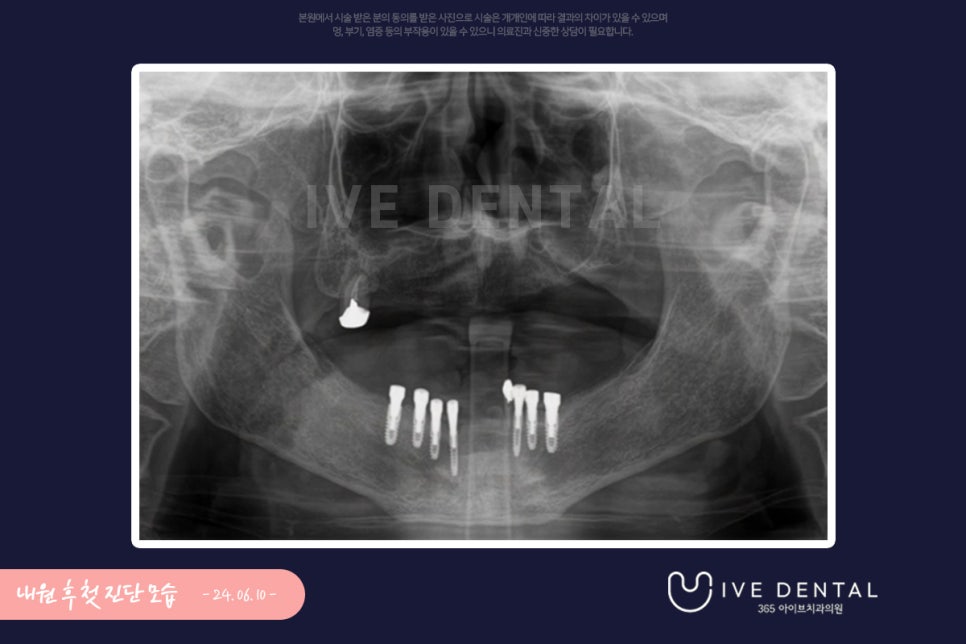

임플란트 재시술을 위해 내원하신 60대 여성분

10년 전 임플란트 시술을 하시고 틀니를 사용 중인 분으로 잇몸 통증이 지속해서 발생하여

임플란트 재시술을 위해 내원하신 60대 여성 환자분이셨습니다.

사진을 보시다시피 치아가 없는 상태이며 잇몸에도 뼈가 거의 남아있지 않았습니다.

이전에 임플란트를 몇 개 시술하시긴 했으나 보철물이 이미 다 탈락하여 있고 재사용이 어려운 상태였습니다.